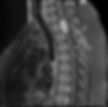

Os sintomas estão relacionados ao local do sistema nervoso afetado pelo seu crescimento. Quando na coluna (figura 1 - imagem branca brilhante), podem simular dores de hérnia de disco, dão paralisia nas pernas, dormência e impotência sexual. Em casos mais avançados, podem deixar o indivíduo paraplégico. Quando crescem no crânio (figura 2 - imagem branca brilhante), mais comumente podem dar dores de cabeça, vômitos, paralisia de alguma parte do corpo, crises convulsivas, sonolência e apatia, como se fosse um quadro de depressão, tonturas acompanhadas ou não por surdez ou zumbido no ouvido, perda da visão ou perda de equilíbrio. Vale a dica: fique atento para investigar uma labirintite, um quadro de depressão ou dores de cabeça. Pode ser um tumor cerebral!

O diagnóstico dessas lesões requer obrigatoriamente um exame de imagem: tomografia ou ressonância magnética. Esses exames auxiliam o médico a localizar a lesão, ver seu tamanho, as estruturas afetadas e planejar seu tratamento. Há diversos locais onde ele pode crescer dentro do crânio, conforme podemos ver na figura 3. Demais exames podem ser solicitados a partir do diagnóstico inicial e de acordo com o que o médico neurocirurgião considerar importante para a segurança do paciente no momento da cirurgia.